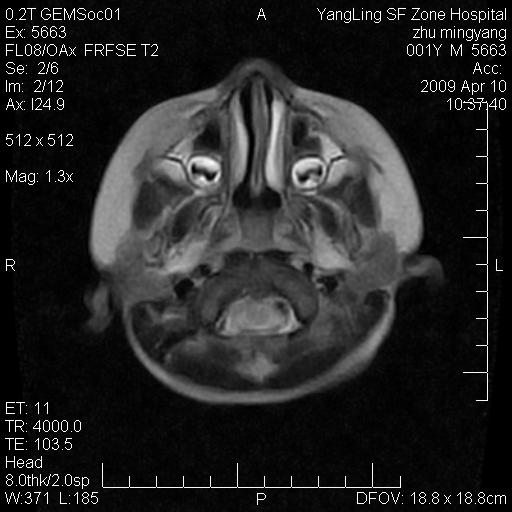

患者:1岁半,两天前外伤收住我院,ct检查小脑占位

考虑星形细胞瘤,建议增强

髓母细胞瘤或血管母细胞瘤,增强后可以鉴别;影像资料见 <。鱼博浪老师的《中枢神经系统ct与mr鉴别诊断》 小脑部肿瘤章节。

髓母细胞瘤或血管母细胞瘤!支持!

支持考虑髓母细胞瘤

考虑----髓母细胞瘤可能性大

考虑髓母细胞瘤或室管膜瘤。

支持髓母细胞瘤。

考虑髓母细胞瘤。

考虑髓母细胞瘤或星形细胞瘤

考虑髓母细胞瘤.

考虑髓母细胞瘤可能性大。

小脑肿瘤.考虑髓母细胞瘤可能.

就病灶部位及临床资料首先考虑髓母.